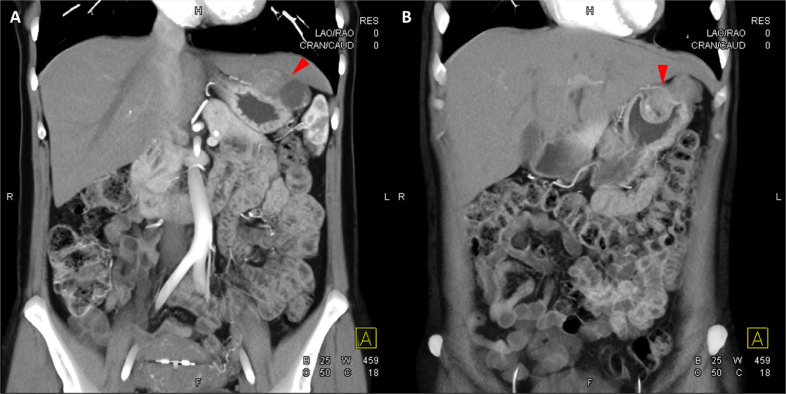

Fig. 4

圖 4: 胃腸道間質(zhì)瘤的三維表示。 (A 和 B)胃腸道間質(zhì)瘤在動脈期和冠狀面的 3D 可視化提供了進(jìn)一步的解剖細(xì)節(jié)和空間信息。